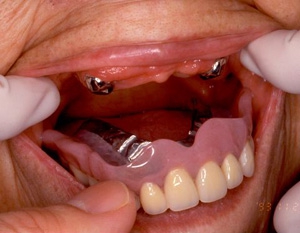

術前術前主訴-総入れ歯の安定が悪い 即時加重可能のミニインプラント使用した。 術前レントゲン術前レントゲン術前レントゲン CT撮影から3次元骨モデルを作成CT撮影から3次元骨モデルを作成CT撮影から3次元骨モデルを作成し埋入位置の確認 フィクスチャーを浸潤麻酔下で埋入フィクスチャーを浸潤麻酔下で埋入。歯茎を切らないので患者さんも非常に楽

4本埋入終了4本埋入終了4本埋入終了(このシステムは4本が絶対条件) 義歯の調整義歯の調整当日に義歯の調整に取りかかる。裏側より義歯をくりぬき維持部のカバー(ハウジング)を義歯の内面に埋め込む step1 義歯の調整義歯の調整当日に義歯の調整に取りかかる。裏側より義歯をくりぬき維持部のカバー(ハウジング)を義歯の内面に埋め込む step2 義歯の調整当日に義歯の調整に取りかかる。裏側より義歯をくりぬき維持部のカバー(ハウジング)を義歯の内面に埋め込む step3

義歯の調整義歯の調整当日に義歯の調整に取りかかる。裏側より義歯をくりぬき維持部のカバー(ハウジング)を義歯の内面に埋め込む step4 義歯の調整義歯の調整当日に義歯の調整に取りかかる。裏側より義歯をくりぬき維持部のカバー(ハウジング)を義歯の内面に埋め込む step5 義歯の裏側義歯の裏側義歯の裏側 装着後しっかり噛める様になる